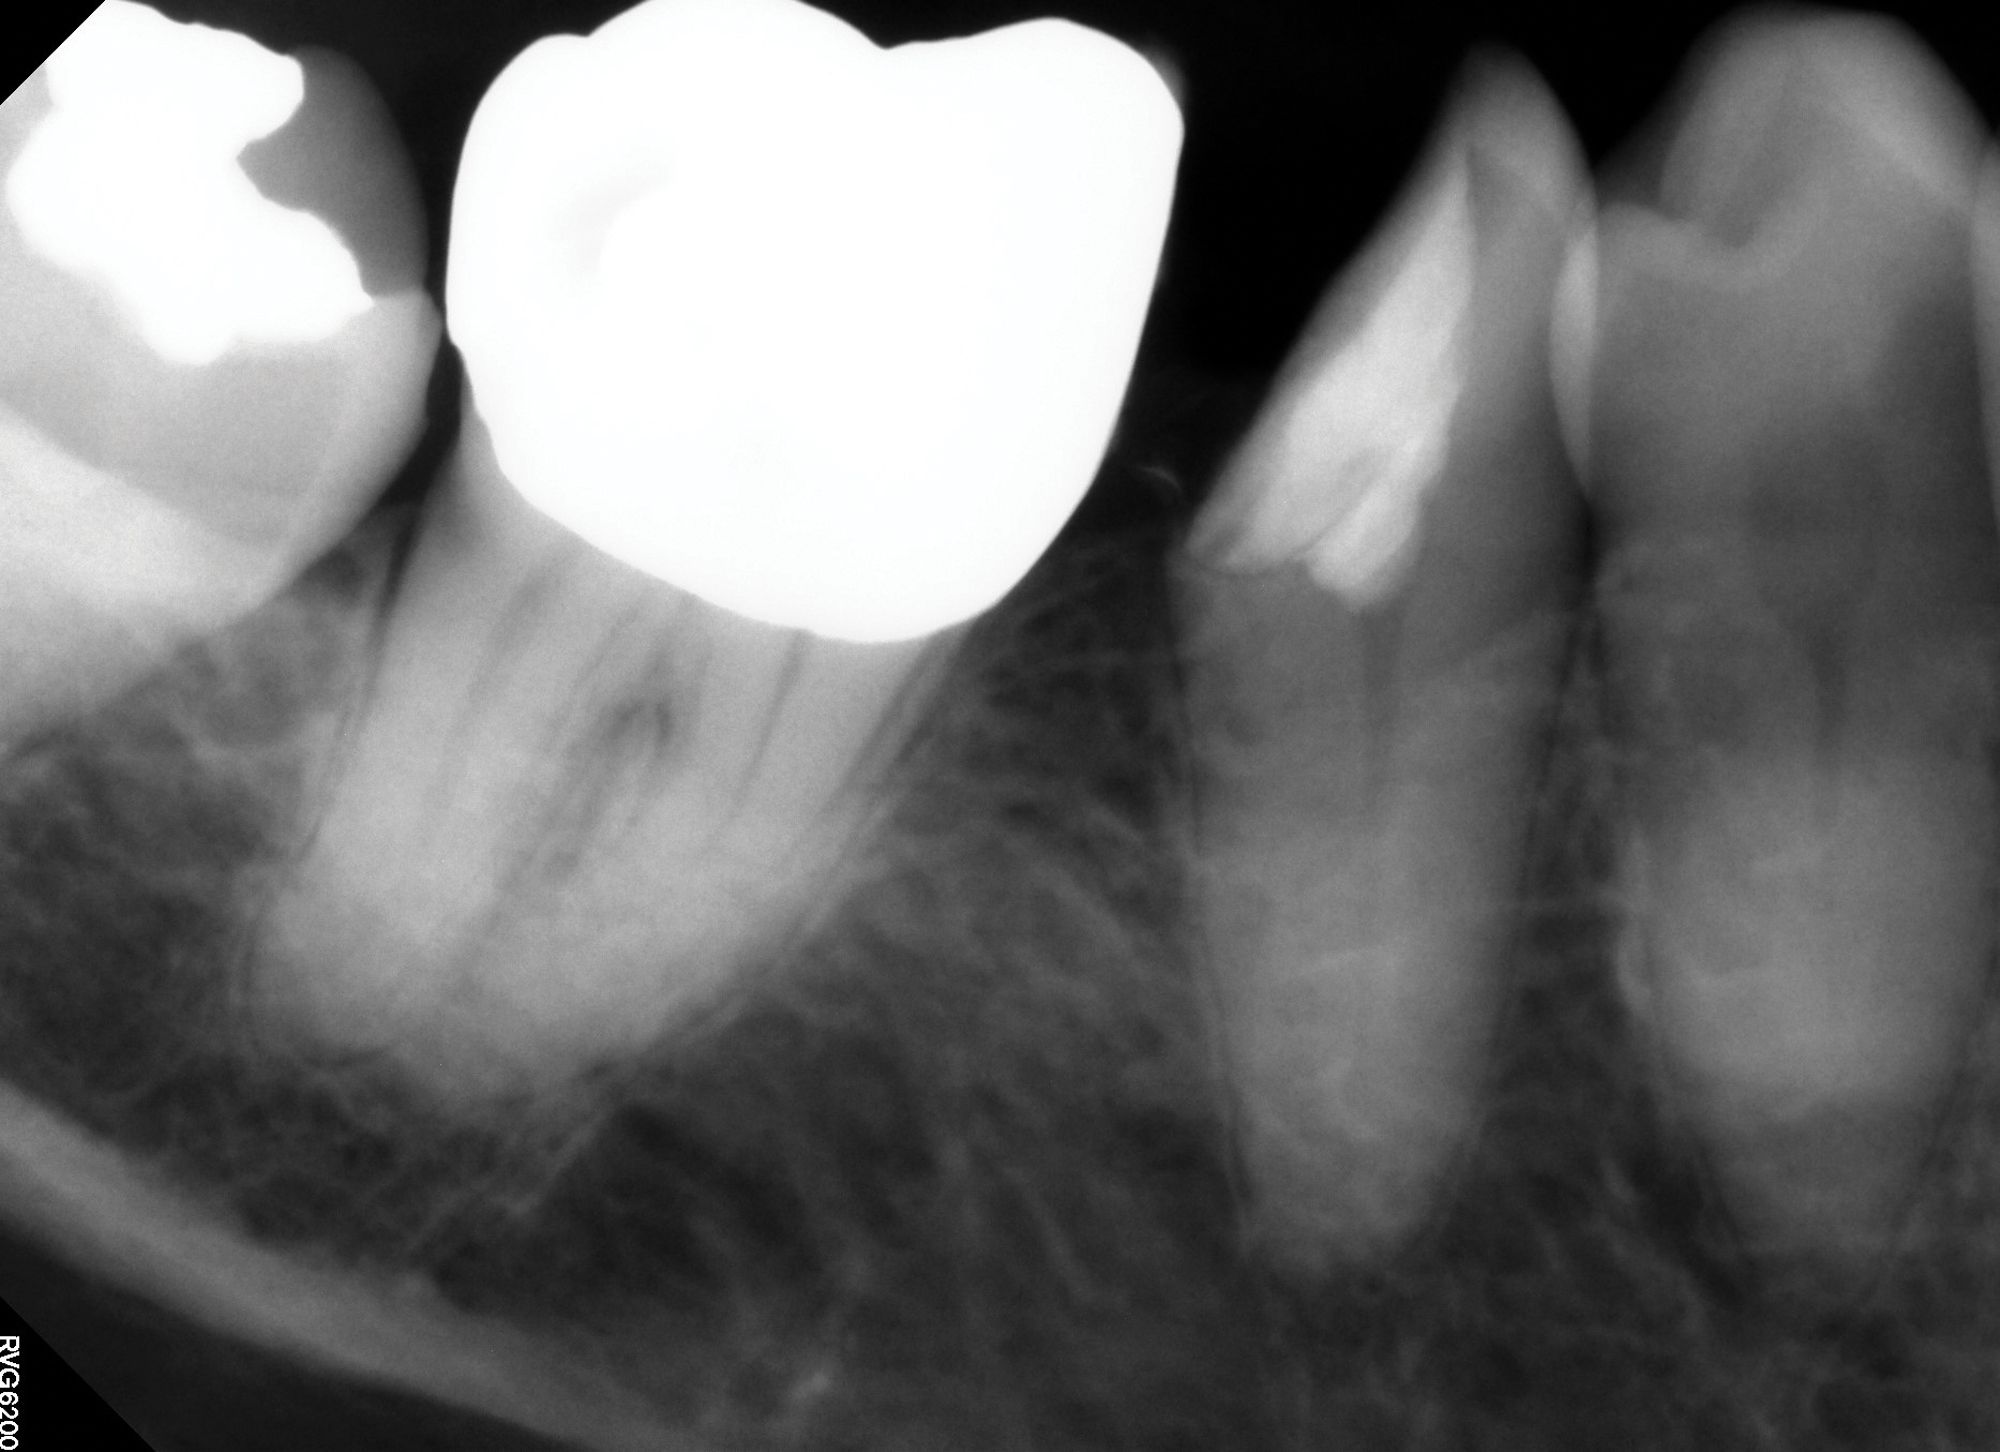

Figure 1A

Figure 1B

Figure 1C. Preoperative images (A and B) depicting deep caries in tooth No. 2 without associated symptoms or clinical testing abnormalities allowed for conservative direct pulp capping to manage the carious exposure (C).